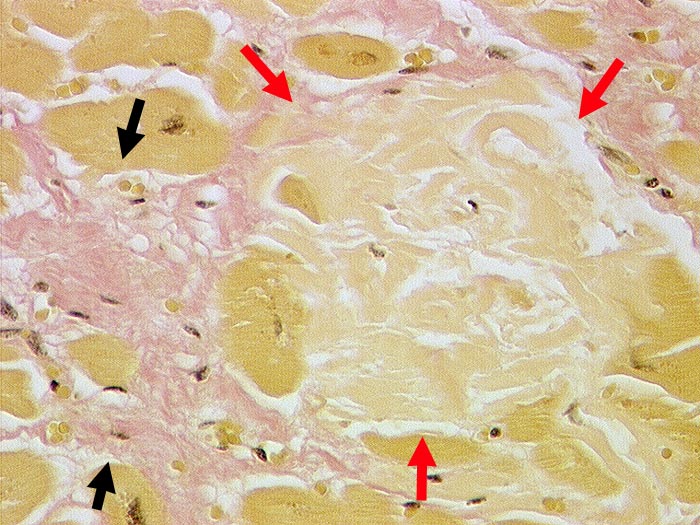

PathoPic ID 252 - Senile Amyloidose des Myokards

Senile Amyloidose des Myokards

Systemerkrankung/Immunpathologie

Herz links

Kardiovaskuläres System

Scholliges azelluläres

►

Amyloid zwischen den Myokardfasern. Daneben

feinfleckige Fibrose.

Koronare Herzkrankheit. Arterielle Hypertonie.

Histologie

89